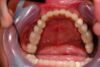

Patientin mit behandelter CMD erhält nach 10 Jahren eine neue vollkeramische Teilkrone

Die Patientin ist bereits seit der Eingliederung der Laborgefertigten Dauerprovisorien, amit über 10 Jahre dokumentiert vollkommen beschwerdefrei!

Sicherlich kommt bei Patienten immer mal wieder die Frage auf, woher man denn weiß, wie sich diese Fälle, nach Abschluss der funktionstherapeutischen Rekonstruktion dannweiter entwickeln!

Indem viele dieser Patienten nachfolgend im "CMD-CENTRUM-KIEL" in "Nachsorgeprogramme" eingebunden sind, deren Ziel darin besteht, dem Patienten diese aufwändigen Arbeiten über Jahre und Jahrzehnte, möglichst bis zum Lebensende hin zu erhalten!